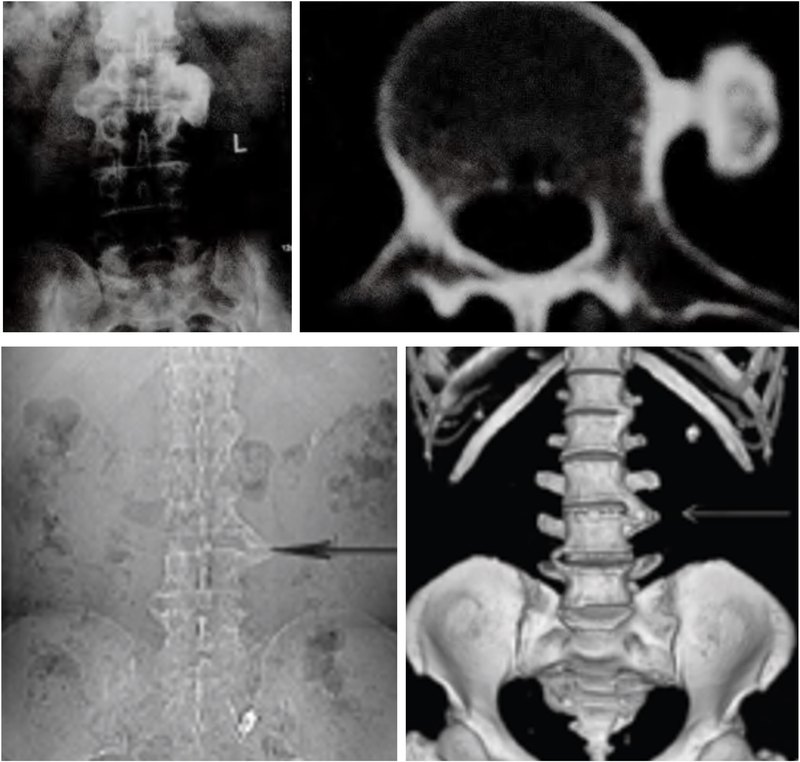

骨软骨瘤病与内生软骨瘤病简介临床上,在所有的良性软骨系统肿瘤中,以骨软骨瘤和内生软骨瘤最为常见。骨软骨瘤和内生软骨瘤多为单发,一旦发病部位达到两处及以上,即可相应诊断为骨软骨瘤病和内生软骨瘤病。这是两种罕见但重要的骨骼疾病,对病人的生活质量和健康状态有着显著的影响,往往在儿童及青少年时期由于骨骼畸形及生长障碍就医而被诊断。成年后,由于关节对位不良,常常导致关节疼痛和退行性变。更为重要的是,尽管两者为良性病变,但均具有恶变为软骨肉瘤的风险。因此,本文将重点介绍这两类疾病的病因、症状、主要治疗方法,以及预防疾病恶变需要注意些什么,供大家学习交流。一、骨软骨瘤病骨软骨瘤病(多发骨软骨瘤),又被称为遗传性多发性外生骨疣(MultipleHereditaryExostoses,MHE),是一种常染色体显性遗传病。它主要表现为多个外生骨疣(即骨软骨瘤)在骨骼表面背向关节生长,这些外生骨疣可以在全身各处出现,但尤其常见于长骨的干骺端,如股骨、胫骨和肱骨,也常见于中轴骨,如骨盆、肩胛骨和脊柱。1.遗传特点骨软骨瘤病的发生与EXT1或EXT2基因的突变有关,约70-94%的多发骨软骨瘤病患者存在EXT1/2胚系突变。EXT1基因在染色体8q24区域,EXT2基因位点在11p11-13,骨软骨瘤病以EXT1突变更为常见。EXT基因编码的蛋白质Exostosin参与了细胞表面的分子信号传导,包括对多种生长因子的组织分布及生物有效性的调节。当EXT1或EXT2基因突变时,会影响软骨细胞的信号传导,导致软骨细胞过度增殖和骨骼发育异常。骨软骨瘤病作为显性遗传病,意味着只要父母中有一方携带这种突变基因,子女就有同等几率患病。两个显著的特点为,(一)、男性患者由于青春期长,生长板闭合较晚,因此一般男性畸形程度较女性重。(二)、EXT1基因突变的患者表型特征更突出,无论男女,身体骨软骨瘤的数量、肢体的短缩程度、身材矮小程度和中轴骨受累的几率都比EXT2基因突变更为明显(p<0.0005)(JBoneJointSurgAm,2011;ClinOrthopRelatedRes,2015)。2.临床表现骨软骨瘤病通常在儿童时期发病,随着骨骼的生长,外生骨疣的数量和大小会逐渐增加。患者主要症状包括:1)骨骼畸形和身材矮小:骨软骨瘤会导致骨骼生长异常和畸形,从而影响身高。2)疼痛和功能障碍:骨软骨瘤可能会压迫周围的肌肉、肌腱、神经和血管,导致疼痛和功能障碍。3)关节活动受限:骨软骨瘤会影响关节活动,导致关节活动受限。4)恶变风险:虽然骨软骨瘤病是良性疾病,但仍有恶变为软骨肉瘤的风险,这种恶变通常发生在成年患者身上,恶变率为5%左右。意大利Rizzoli研究中心研究了多发性骨软骨瘤的基因型-表型的相关性,调查了529名患者,将患者分为轻、中和重三型(如下表),26例恶变患者多发骨软骨瘤的诊断年龄平均为7.6岁,恶变诊断年龄平均为28.6岁。恶变为软骨肉瘤的部位最多见于骨盆和肩胛骨,但未发现恶变的风险与性别、畸形程度、骨软骨瘤的数量以及EXT1/2突变显著相关(JBoneJointSurgAm,2011)。3、临床分型临床上按照患者表型特征分为轻(I型),中(II型)和重(III型)三型。529患者中1/4为重型,其他3/4为轻中型(轻/中型约1:1)。(来自JBoneJointSurgAm,2011)典型病例男性,29岁,自幼诊断为多发骨软骨瘤,因骨盆部位包块入院,术前检查怀疑骨盆骨软骨瘤恶变,手术行肿瘤切除,保留髋关节后柱,股骨头髋臼重建,假体置换,术后病理确诊软骨肉瘤I级,现为术后10年,肿瘤未复发,功能良好。随访10年行走视频二、内生软骨瘤病内生软骨瘤病(多发内生软骨瘤,Enchondromatosis)是一种非遗传性基因突变导致的疾病,主要特征为骨内多处出现内生软骨瘤。这些软骨瘤通常是良性的,但在某些情况下可以恶变为软骨肉瘤。Ollier病和Maffucci综合征是内生软骨瘤病最常见的两种类型。Ollier病:以多发性内生软骨瘤为特征,通常累及长骨和扁平骨,如股骨、胫骨、骨盆等。患者可能在儿童时期就表现出症状,随着骨骼成熟,软骨瘤的数量和大小可能会增加。Ollier病患者除了骨骼畸形外,还可能面临骨折和疼痛的风险。Maffucci综合征:即软骨营养障碍-血管瘤综合征,是一种更为罕见的内生软骨瘤病,其特点是多发性内生软骨瘤与多发性软组织血管瘤同时存在。血管瘤通常位于上肢,如手部和前臂,但也可能出现在下肢和躯干。Maffucci综合征患者除了骨骼畸形外,还可能面临血管瘤破裂出血和内生软骨瘤恶变为软骨肉瘤的风险。女性,63岁,Maffucci综合征,骨盆及股骨近远端受累,股骨畸形。左侧骨盆内生软骨瘤恶变为软骨肉瘤。1.遗传特点内生软骨瘤病的病因尚未完全明确,但研究表明,非遗传性基因突变起着重要作用。IDH1基因位于染色体2q33.3,IDH2基因在15q26.1,IDH基因编码一种酶称为异柠檬酸脱氢酶,这种酶在细胞内催化异柠檬酸转化为α-酮戊二酸。IDH1/2突变见于81%Ollier病和77%Maffucci综合征患者。IDH1突变常见的类型是在IDH1基因的第132位氨基酸发生突变,替换了精氨酸(arginine,R)为组氨酸(histidine,H),因此被称为R132H突变。IDH2基因突变发生在第四外显子的R140和R172。IDH1/2突变导致酶活性的异常改变,使其催化产物从α-酮戊二酸转变为2-羟戊二酸(2-hydroxyglutarate,2-HG),细胞内促癌代谢产物2-HG异常积累,影响骨骼发育,导致内生软骨瘤的形成。需要强调的是,内生软骨瘤病并非遗传性疾病,因此患者的家族成员通常不会患病。2.临床表现内生软骨瘤病早期通常不伴明显症状,随着骨骼的生长,内生软骨瘤的数量和大小也会逐渐增加。患者可能出现骨骼畸形、关节活动受限等症状。在严重病例中,软骨瘤可能累及整个骨骼系统,导致严重的残疾。此外,与骨软骨瘤病类似,内生软骨瘤病也存在恶变为软骨肉瘤的风险。恶变率因病情严重程度而异,但总体上高于骨软骨瘤病,其中在Maffucci综合征患者中,恶变率甚至高达50%以上。因此,内生软骨瘤病患者同样需要定期复查。三、治疗方法与管理策略目前,对于骨软骨瘤病和内生软骨瘤病尚无有效的药物治疗方法。对于无症状或症状轻微的患者,通常无需治疗,只需定期随访观察。然而,当骨疣或内生软骨瘤压迫周围组织、引起疼痛或关节活动受限时,手术治疗是可供选择的手段,手术方法包括切除骨疣、矫正畸形等。对于成年患者和恶变风险较高的患者,定期复查尤为重要。通过X线、CT和MRI等影像学检查手段,可以及时发现并处理恶变病灶。四、骨软骨瘤病和内生软骨瘤病的异同五、总结与展望因此回到本文的标题上,骨软骨瘤病是遗传性疾病,而内生软骨瘤病是非遗传性疾病。二者均是罕见的骨骼疾病,虽然它们是良性的,但仍有恶变为软骨肉瘤的风险。定期随访和及时治疗可以帮助预防恶性变,改善患者的预后。